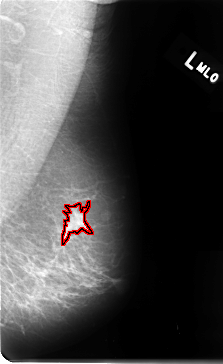

B_3058_1.LEFT_MLO

FILE: B_3058_1.LEFT_MLO.OVERLAY

TOTAL_ABNORMALITIES 1

ABNORMALITY 1

LESION_TYPE MASS SHAPE IRREGULAR-ARCHITECTURAL_DISTORTION MARGINS SPICULATED

ASSESSMENT 4

SUBTLETY 4

PATHOLOGY MALIGNANT

TOTAL_OUTLINES 1

BOUNDARY